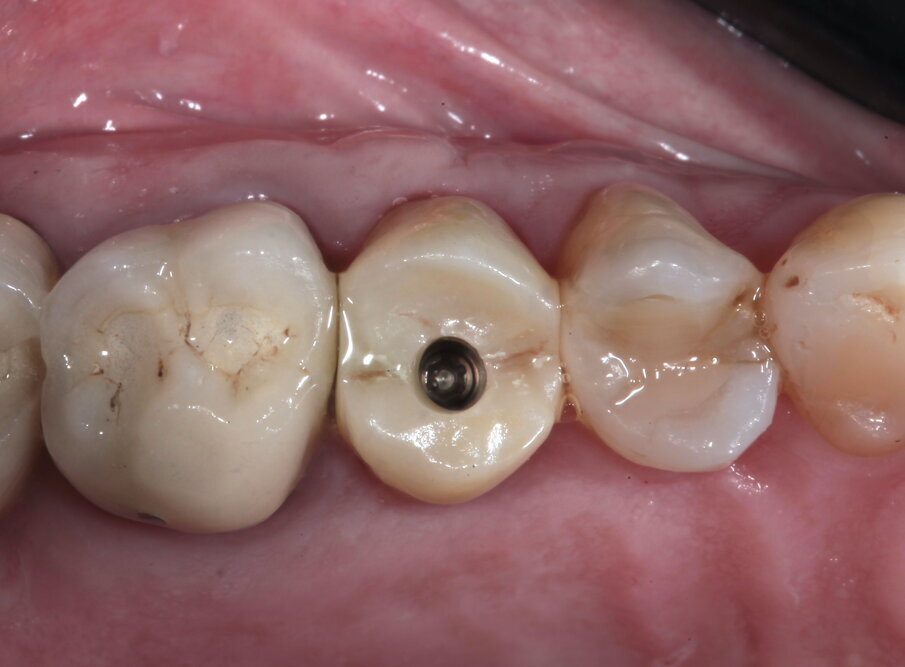

La paziente si presenta in visita lamentando mobilità e l’insorgenza di un dolore alla masticazione a carico dell’elemento 25. Clinicamente l’elemento presenta una corona in ceramica integrale realizzata anni prima (non ricorda quanti) presso altra sede, mobilità di II grado e sondaggio di 9 mm sul versante palatale.

Si presenta inoltre dolente alla percussione. Si riscontra anche l’assenza di risposta al test di vitalità dell’elemento 24, sul quale la paziente riferisce sia stata effettuata una medicazione endodontica da un collega come tentativo di risolvere la sintomatologia dolorosa a carico dell’elemento 25 (Figg. 1-3).